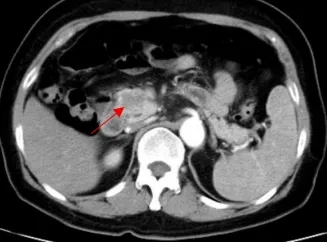

箭头示为患者三的胰头部恶性肿瘤

箭头示为患者三的腹膜后肿瘤 延伸至盆腔